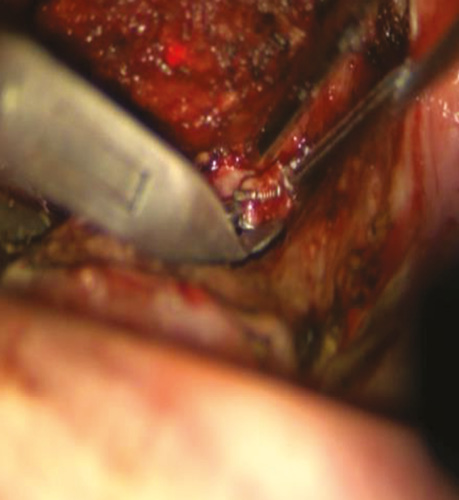

Пацієнт С., 56 років. Діагностовано плоскоклітинну карциному передньої піднебінної дужки з поширенням на корінь язика T2N0M0. Проведено трансоральну CO₂-лазерну резекцію бічної стінки ротоглотки та кореня язика доступом через сформоване «вікно» в ділянці дна ротової порожнини. На рис. 3–6 наведено етапи хірургічного втручання.

Рис. 5. Виділено та кліповано a. dorsalis linguae